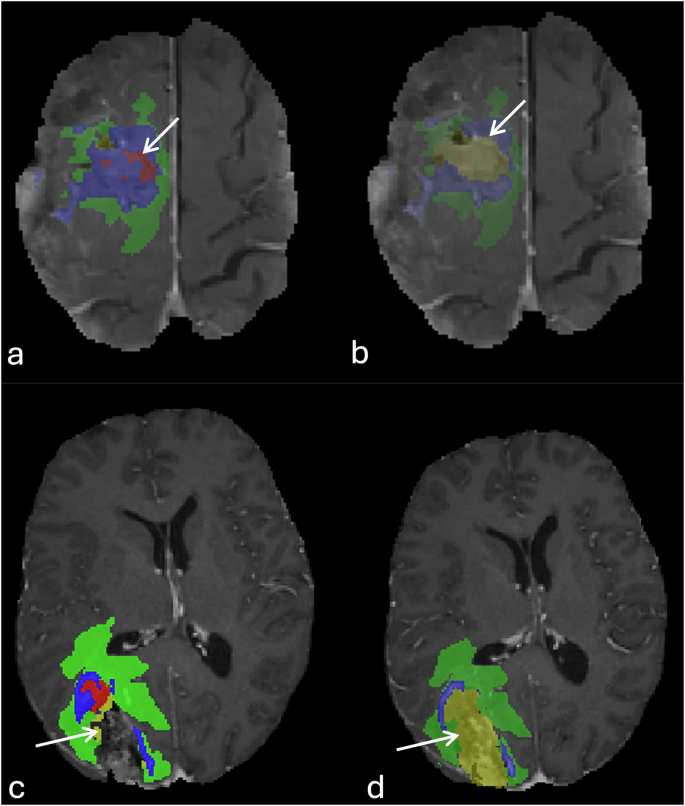

Erroneous inclusion of T1 hyperintensity and misclassification as enhancing tumor component (Fig. 5).

Fig. 5 Misclassification of the T1 shortening of the resection cavity rim as enhancing tumor label. Peripheral T1 hyperintensity of the anteromedial and posteromedial margins of the resection cavity (a), without change in T1 following IV gadolinium-based contrast administration (b). Note wrong assignment of the enhancing tumor label (blue, c).

T1 hyperintense signals within the resection cavity were incorrectly and misclassified as non-enhancing hemorrhagic tumor component instead of blood products within the resection cavity (Fig. 6).

Fig. 6 An example of misclassification of T1 hyperintensity within the center of the resection cavity. T1 hyperintense material within the resection cavity with fluid level, and foci of pneumocephalus without corresponding enhancement (arrows, a & b). The segmentation overlay image shows the wrong assignment of the T1 hyperintensity as enhancing tumor (blue), and non-enhancing tumor core (red).